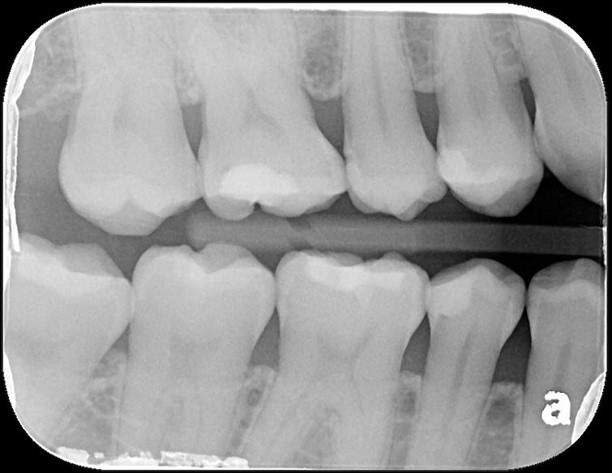

X光可見小臼齒與大臼齒之間有蛀洞

治療後,X光密合度良好